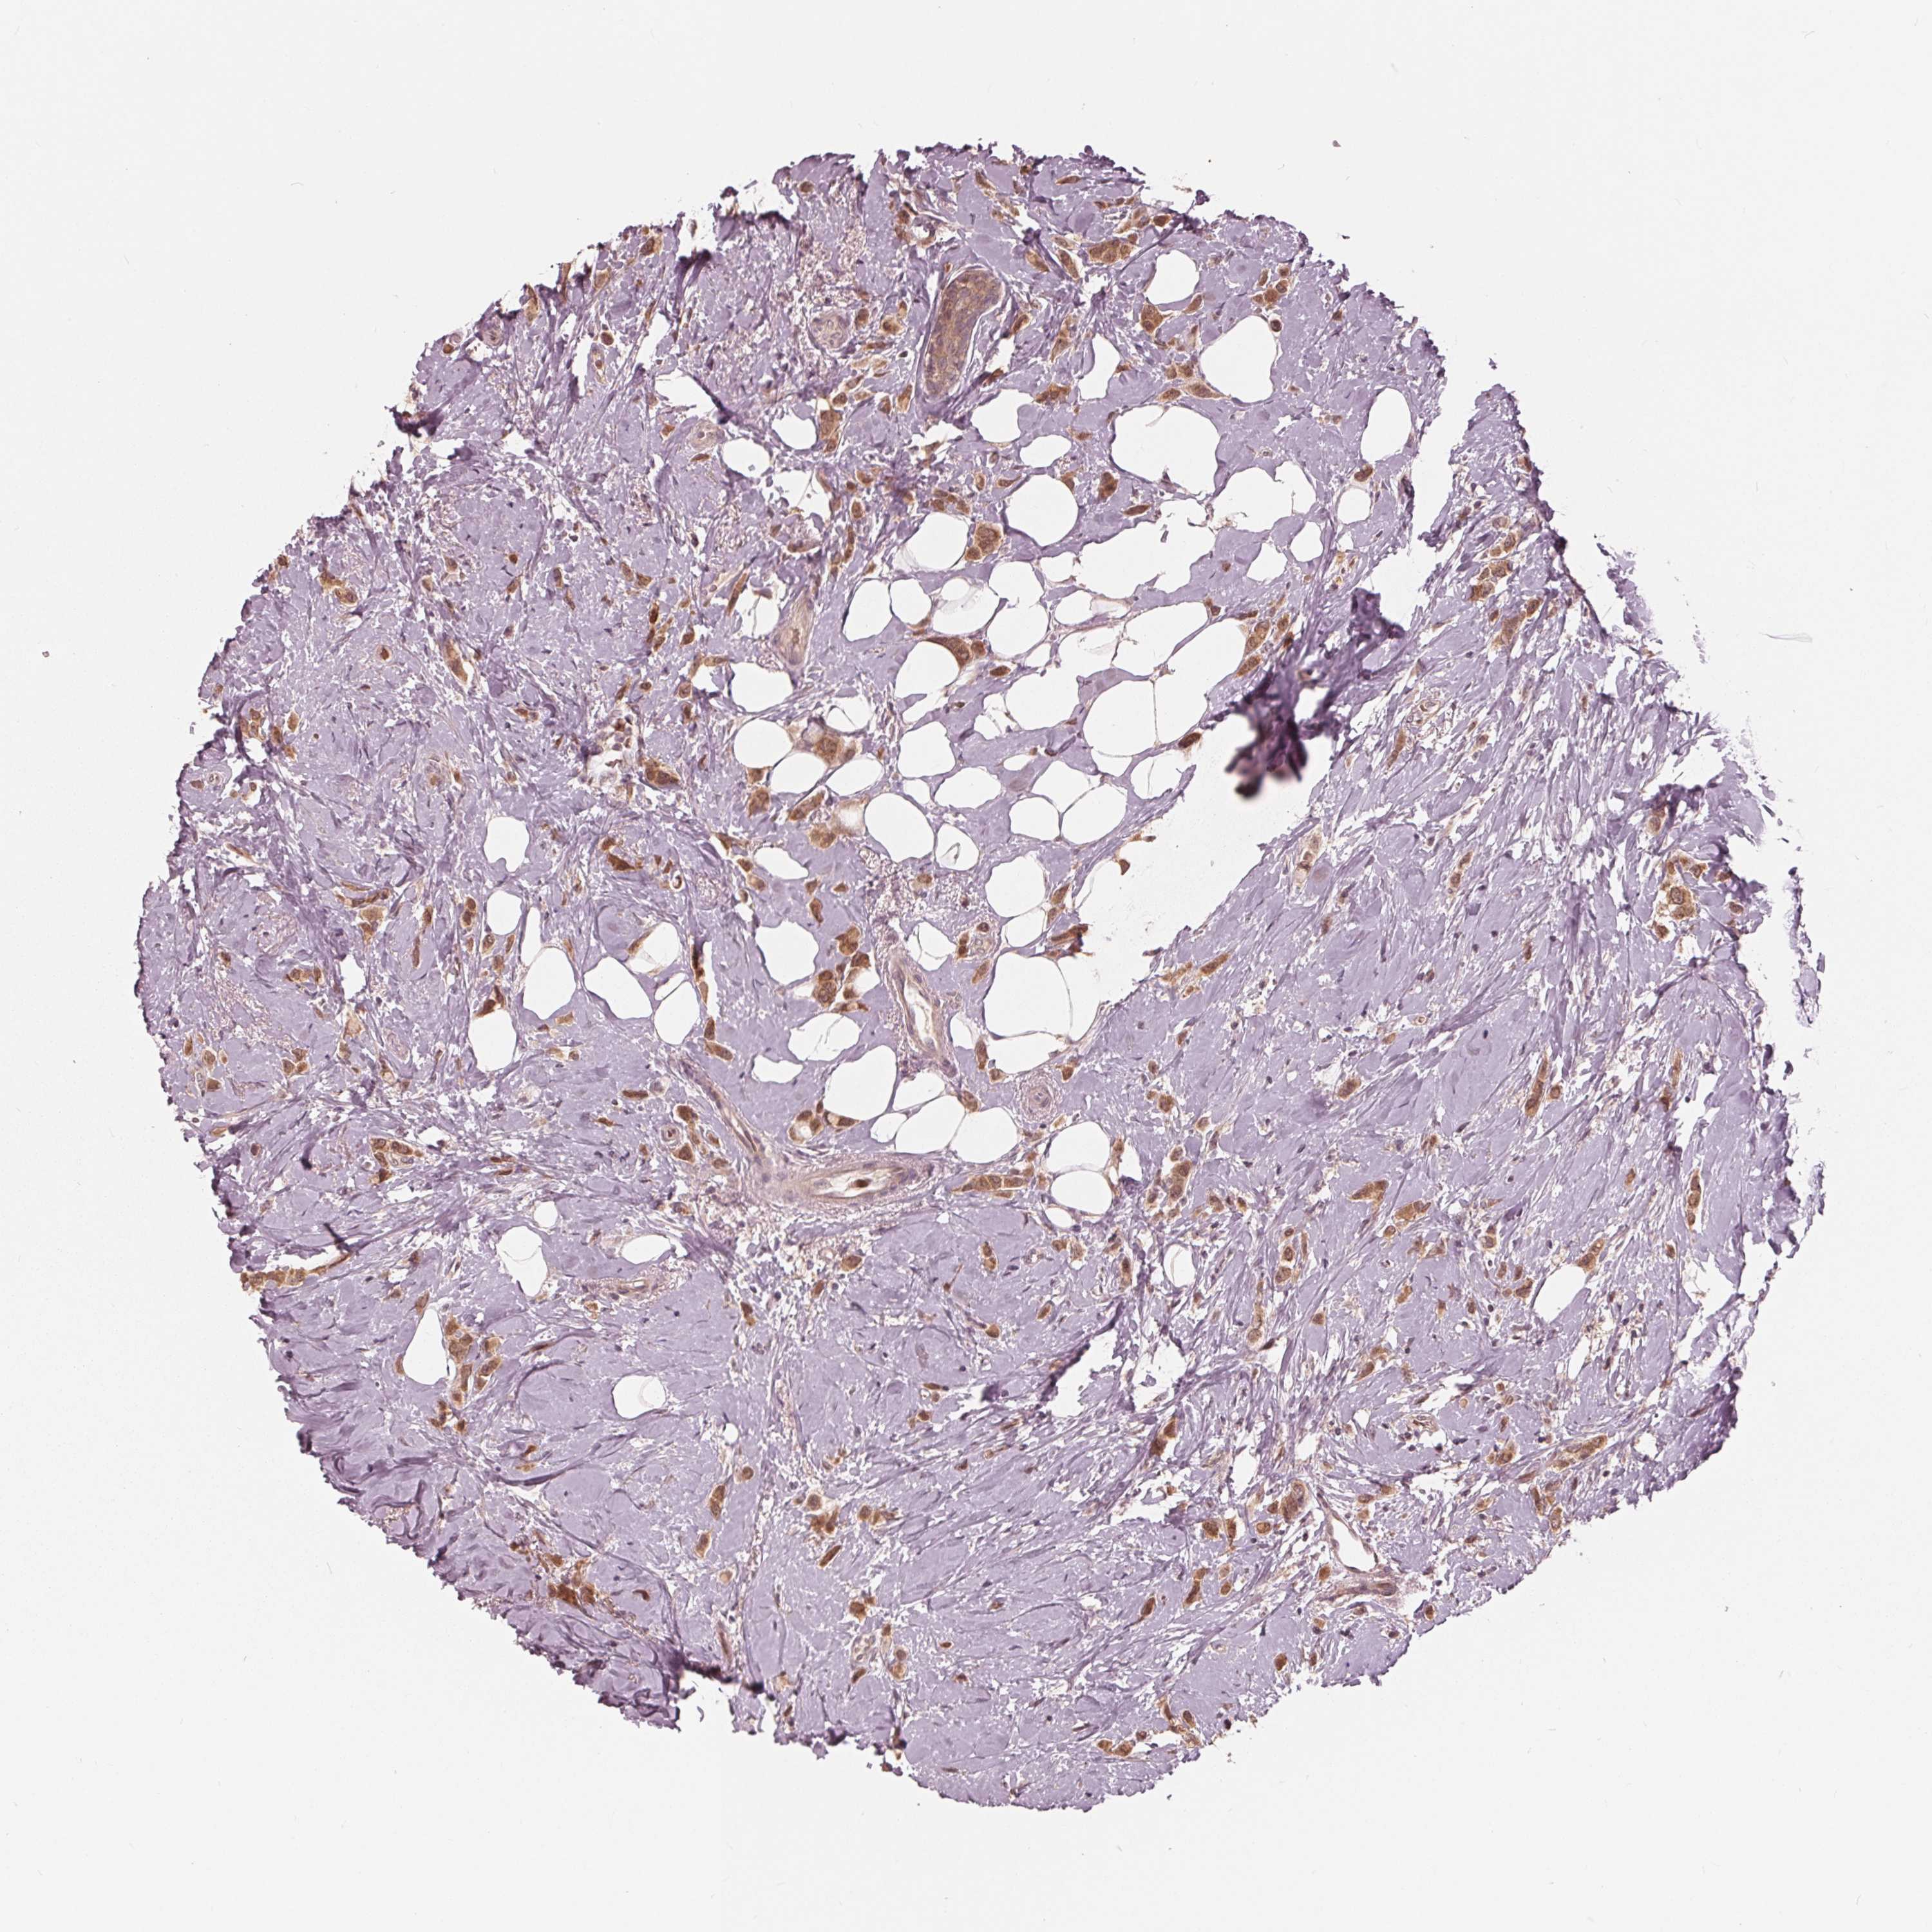

CANCER BREAST CANCER Show tissue menu

BRCA TCGA BRCA VALIDATION PROTEIN EXPRESSION

ANTIBODIES

AND

VALIDATION